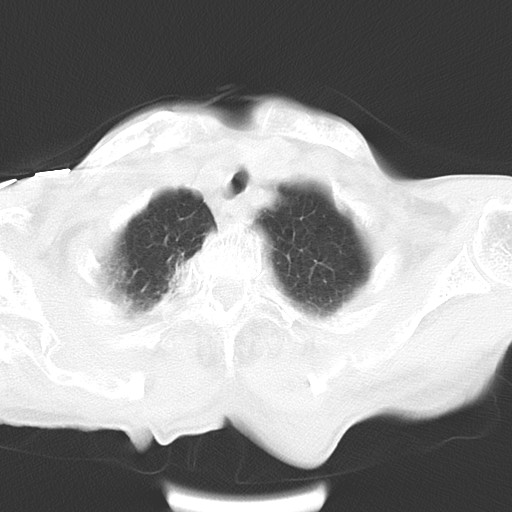

女,93岁,摔伤后检查。

右肺炎症,心功能不全伴双侧胸腔积液,右下肺膨胀不全,食管裂孔疝,冠脉钙化,心包少量积液,左侧肋骨骨折,请上传骨窗.

右侧锁骨\\肩胛骨骨折、右侧湿肺,心功能不全伴双侧胸腔积液,右下肺膨胀不全,左膈破裂或食管裂孔疝,冠脉钙化,心包少量积液,请上传骨窗.

右肺炎症,心功能不全伴双侧胸腔积液,右下肺膨胀不全,食管裂孔疝,冠脉钙化,心包少量积液,左侧肋骨骨折,右肩甲骨粉碎性骨折。93岁,高寿哇!

右肺炎症,心功能不全伴双侧胸腔积液,右下肺膨胀不全,食管裂孔疝,冠脉钙化,心包少量积液,左侧肋骨骨折,右肩甲骨粉碎性骨折。